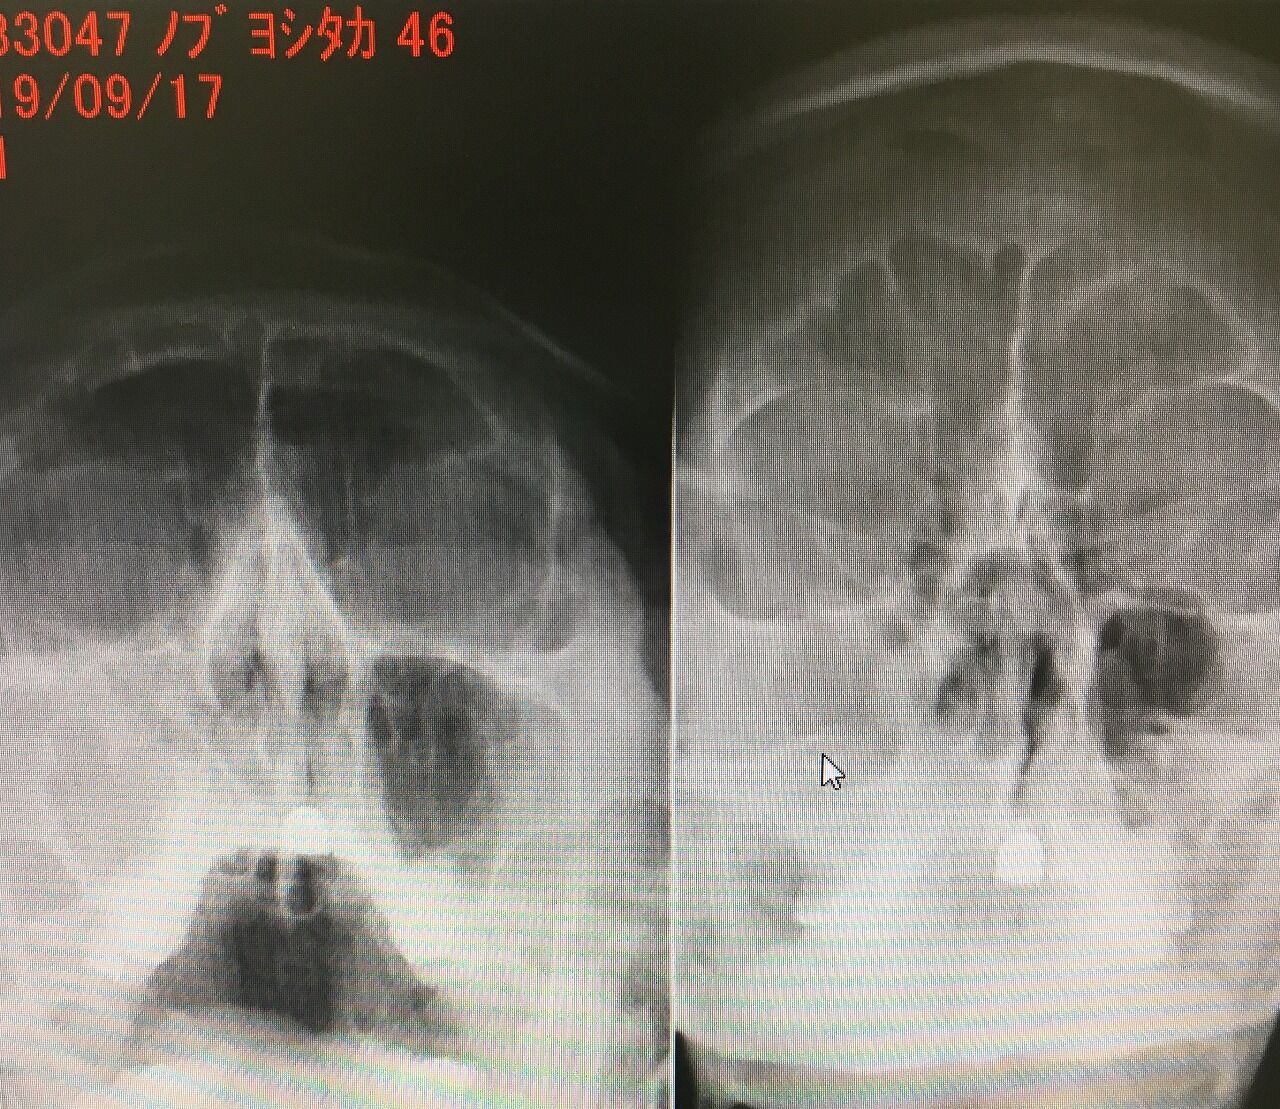

キレイな副鼻腔炎(蓄膿症)のレントゲン写真。